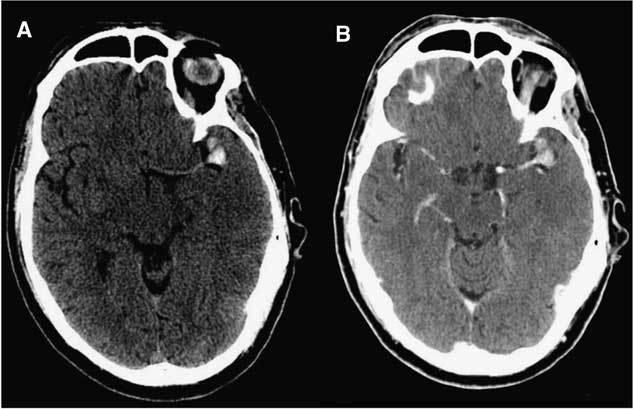

Initial computed tomography (CT) scans demonstrated a thrombosed MCA aneurysm (1.8×1.3×1.0 cm) with associated occlusion of the left MCA at its bifurcation (Figure 1). There was no evidence of subarachnoid hemorrhage or intracerebral blood. There was loss of grey-white differentiation in the left insular, frontal and parietal lobes. The initial Alberta Stroke Program Early CT score was 2, indicating an established stroke with diffuse MCA involvement. As such, stroke mitigation by endovascular or surgical revascularization was not pursued. The next day magnetic resonance imaging (MRI) and MR angiography (MRA) confirmed a large area of ischemic acute infarction in the left MCA territory and extremely poor opacification of distal left MCA branches (Figure 2).

Figure 1 Initial uninfused (A) and infused (B) CT demonstrating hyperdensity at the left MCA bifurcation representing an acutely thrombosed aneurysm with occlusion of the parent vessel and early MCA territory infarction.